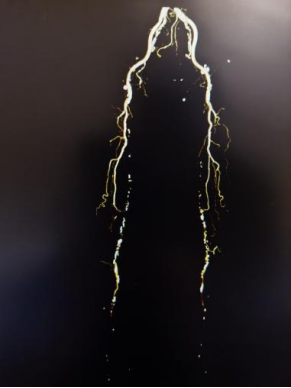

面对严峻病情与家属的殷切期盼,血管外科团队高度重视,联合老年医学科、康复医学科、重症医学科等多学科进行周密会诊评估,反复研判手术方案,精准把控手术指征与风险节点,制定出个体化手术方案。在充分术前准备与严密术中监护下,手术团队凭借精湛技术,为患者开通闭塞血管,恢复下肢血供。

术后,医护团队实行专人专护、精细化管理,从病情监测、疼痛管理、营养支持到康复指导全程跟进。在精心治疗与悉心照料下,患者下肢疼痛明显缓解,缺血症状逐步改善,精神状态日渐好转,避免截肢,重新恢复站立与行走能力。